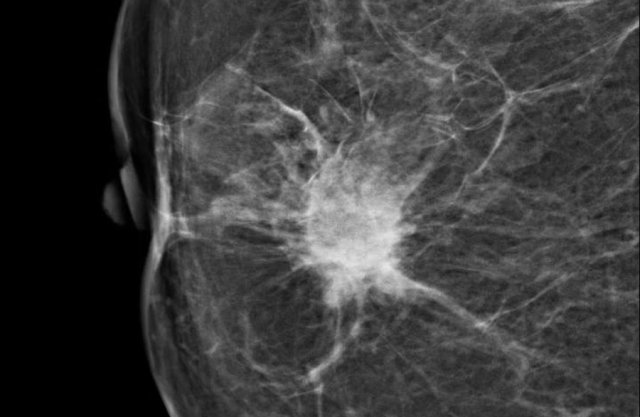

• Spiculated with radiating lines from the mass is a very suspicious finding.

The density of a mass is related to the expected attenuation of an equal volume of fibroglandular tissue.

High density is associated with malignancy.

It is extremely rare for breast cancer to be low density.

Here a hyperdense mass with an irregular shape and a spiculated margin.

Notice the focal skin retraction.

This was reported as BI-RADS 5 and proved to be an invasive ductal carcinoma.